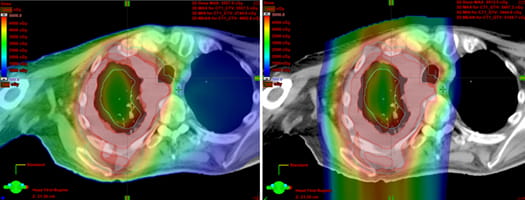

The images below compare the two forms of radiation therapy one UMGCCC mesothelioma patient received.

On the left is traditional radiation therapy, and on the right is proton therapy. The colored areas denote the radiation doses to the patient's chest.

In the proton therapy image, on the right, the normal lung is spared from radiation.